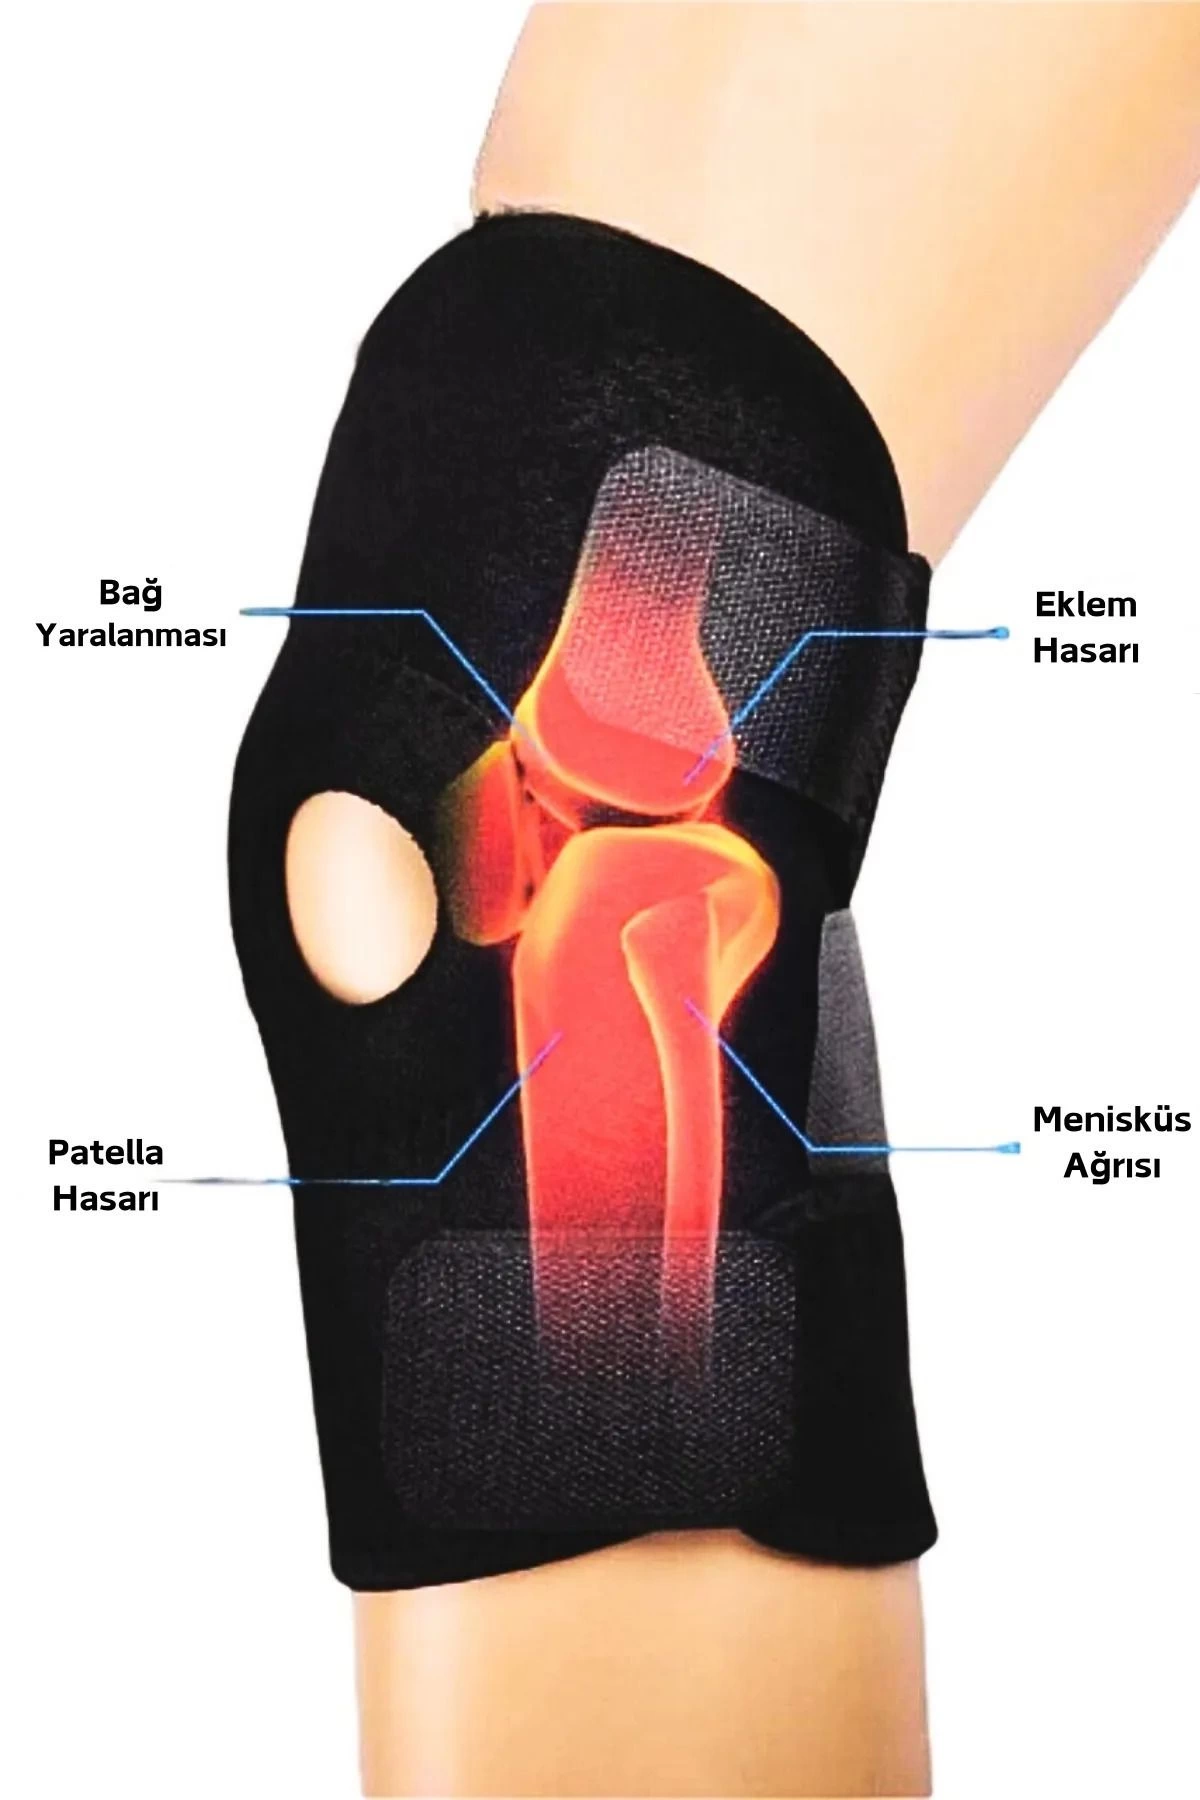

Orijinal fiyat: ₺300.00.₺270.00Şu andaki fiyat: ₺270.00.Diz Korsesi Çapraz Bağ Menisküs Ağrısı Için Dizlik Diz Bandajı Patella Dizlik

Diz Korsesi Çapraz Bağ Menisküs Ağrısı Için Dizlik Diz Bandajı Patella Dizlik

Diz Korsesi, çapraz bağ veya menisküs ağrısı yaşayanlar için ideal bir seçenektir. Patella Dizlik özelliği sayesinde dizinizi destekler ve korur, böylece spor yaparken veya günlük aktivitelerde rahatça kullanabilirsiniz. Bu Diz Bandajı, hafif ve esnek yapısıyla konforlu bir kullanım sunar.

Ürün Özellikleri:

- Çapraz bağ veya menisküs ağrısı olanlar için uygundur.

- Patella Dizlik özelliği sayesinde dizinizi destekler.

- Hafif ve esnek yapısıyla konforlu kullanım sağlar.

Bu Diz Korsesi, Aktif bir yaşam tarzını benimseyenler için ideal bir seçenektir. Diz ağrılarıyla mücadele ederken destek almak isteyenler için bu ürünü tercih edebilirsiniz.